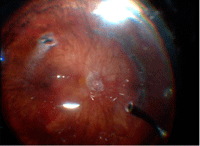

Para obtener la identificación del gel incarcerado en las esclerotomías se realiza el depósito bajo depresión escleral de la esclerotomía permitiendo la identificación completa de las fibras de gel (

Figura 2,

Figura 3, Figura 4 y

Figura 5).

Figura 2. Desprendimiento de retina en Miope magno donde no se aprecia claramente el gel vítreo.

Figuras 3 y 4. Disección de Hialoides posterior ayudado por Triamcilonona y Perfluorocarbono (PFCL) en desprendimiento de retina.